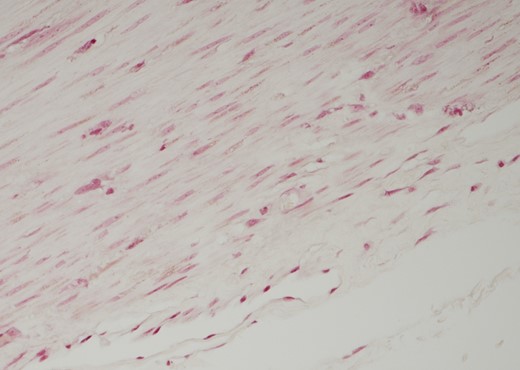

The resected portion of sigmoid colon measured 18 cm in circumference. The muscularis propria showed increased amounts of intracellular lipofuscin, which was perle’s stain negative, and both PAS and PAS/D positive, Fig. 6.

Histology: section of muscularis propria. Staining positive for both PAS and PAS D. Perle’s stain was negative.

These findings supported a diagnosis of intestinal lipofuscinosis.